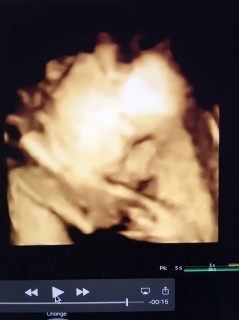

写真:32w1d:ケイトさん:こんなに開いたパー

なかなかお顔を見せてくれない息子ちゃん、今日のエコーでは手のひらを大きく開いてパーをして顔を隠していました(笑)先生もこんなに開いたパーをは珍しいね、と言ってくれました(^^)